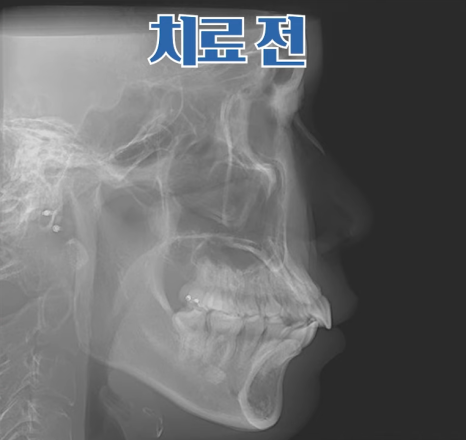

치료 전 X-ray 측면 모습으로도 치아가 앞으로 기울어져 있고,

입이 튀어나온 모습을 확인할 수 있습니다.

치료 전후 X-ray 사진을 비교해 보면,

기울어졌던 앞니가 정상 각도로 줄어들었고 자연스레 돌출입도 개선된 걸 볼 수 있지요.